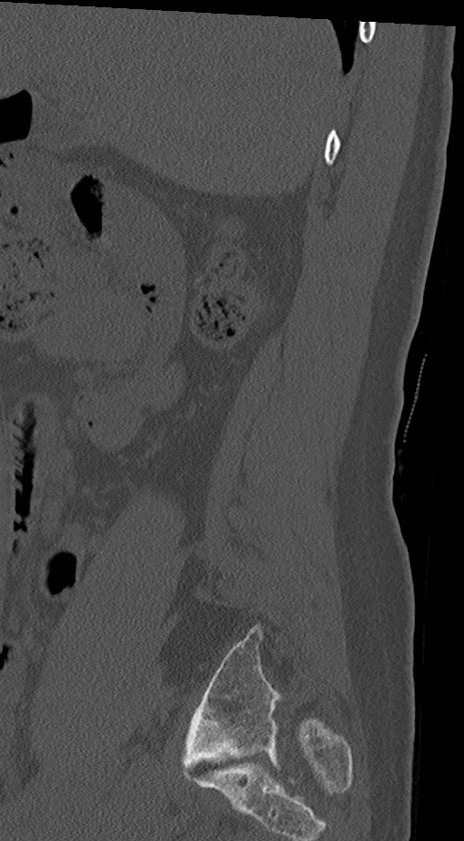

【整形】TIPS症例4 腰椎CT(矢状断像)

腰椎CT

冠状断像